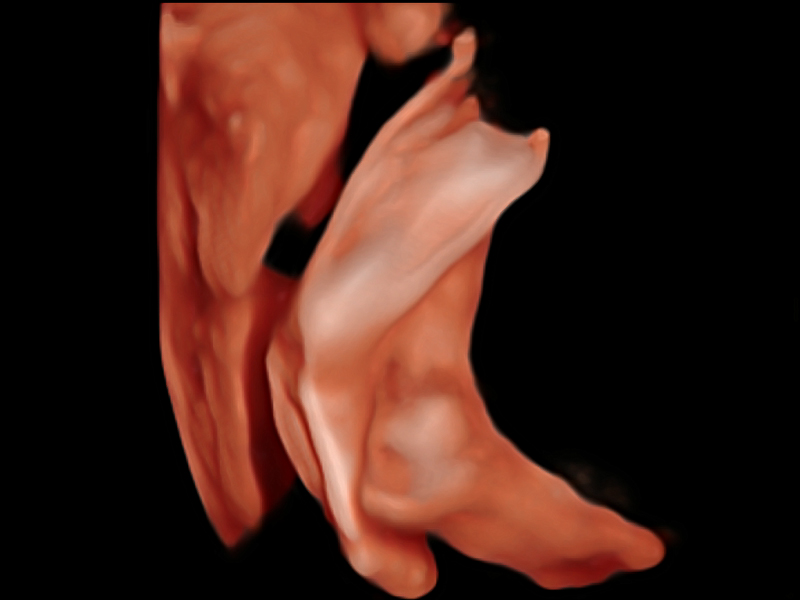

憑借開(kāi)立醫(yī)療先進(jìn)的成像技術(shù)和優(yōu)異的探頭技術(shù)提供的清晰的圖像表現(xiàn),您可以更自信地做出臨床決策。